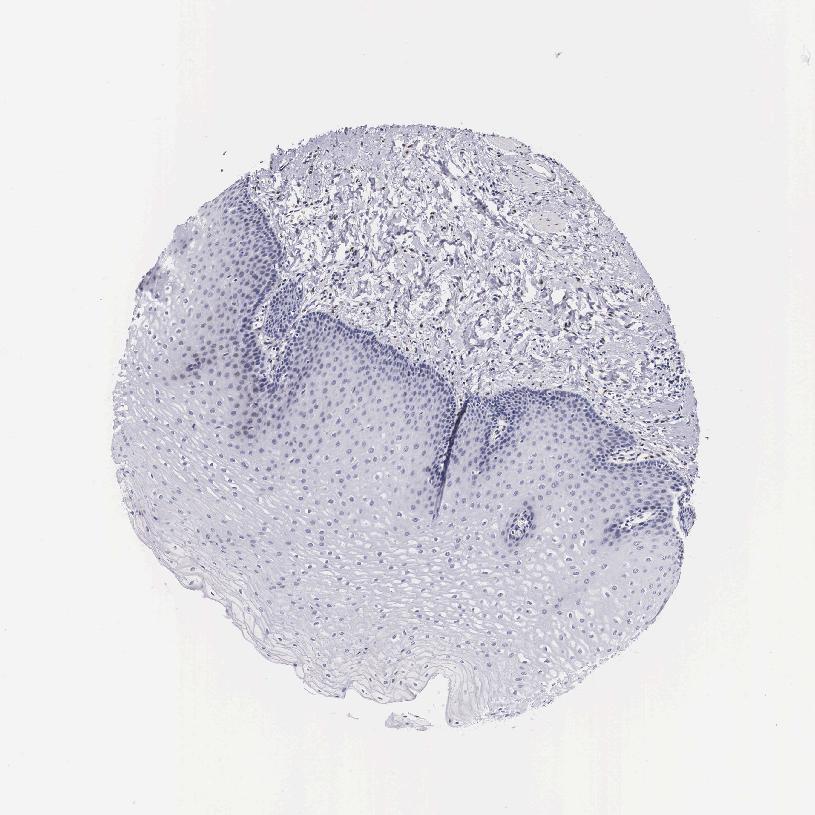

TISSUE PRIMARY DATA ESOPHAGUS Show tissue menu

Esophagus

ESOPHAGUS - Antibody stainingi

Antibody staining in the annotated cell types in the current human tissue is reported as not detected, low, medium, or high, based on conventional immunohistochemistry profiling in selected tissues. This score is based on the combination of the staining intensity and fraction of stained cells.

Each image is clickable and will lead to virtual microscopy that enables deeper exploration of all samples and also displays staining intensity scores, fraction scores and subcellular localization as well as patient and tissue information for each sample.

Antibody HPA000275Antibody HPA000500

Squamous epithelial cells Not detectedNot detected